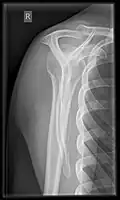

Shoulders

These include:

- AP-projection 40° posterior oblique after Grashey

The body has to be rotated about 30 to 45 degrees towards the shoulder to be imaged, and the standing or sitting patient lets the arm hang. This method reveals the joint gap and the vertical alignment towards the socket.[17]

- Transaxillary projection

The arm should be abducted 80 to 100 degrees. This method reveals:[17]

- The horizontal alignment of the humerus head in respect to the socket, and the lateral clavicle in respect to the acromion.

- Lesions of the anterior and posterior socket border or of the tuberculum minus.

- The eventual non-closure of the acromial apophysis.

- The coraco-humeral interval

- Y-projection

The lateral contour of the shoulder should be positioned in front of the film in a way that the longitudinal axis of the scapula continues parallel to the path of the rays. This method reveals:[17]

- The horizontal centralization of the humerus head and socket.

- The osseous margins of the coraco-acromial arch and hence the supraspinatus outlet canal.

- The shape of the acromion

This projection has a low tolerance for errors and accordingly needs proper execution.[17] The Y-projection can be traced back to Wijnblath's 1933 published cavitas-en-face projection.[18]

In the UK, the standard projections of the shoulder are AP and Lateral Scapula or Axillary Projection.[15]